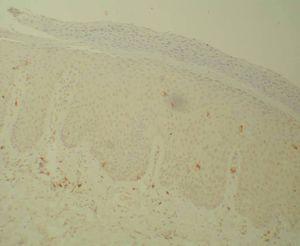

Se analizó un total de 20 biopsias procedentes de 10 pacientes. La cuantificación de las poblaciones linfocitarias totales, en el estrato dérmico y en el estrato epidérmico, se muestran en la tabla 1. Hubo un descenso significativo en las distintas poblaciones linfocitarias tras el tratamiento con etanercept. Los linfocitos CD4 totales basales y tras tratamiento con etanercept mostraron 16,93 ± 8,13 frente a 6,51 ± 3,46, p < 0,007; y los linfocitos CD8 totales basales y tras tratamiento (figs. 1 y 2) con etanercept: 17,73 ± 9,77 frente a 10,50 ± 9,46, p < 0,005. Los linfocitos CD4 basales en dermis y tras tratamiento con etanercept registraron 14,46 ± 6,42 frente a 6,11 ± 3,41, p < 0,007; y los linfocitos CD8 basales en dermis y tras tratamiento con etanercept: 17,29 ± 7,17 frente a 11,57 ± 6,50, p < 0,005. Los linfocitos CD4 basales en epidermis y tras tratamiento con etanercept registraron 2,47 ± 2,18 frente a 0,40 ± 0,29, p < 0,008; y los linfocitos CD8 basales en epidermis y tras tratamiento con etanercept: 17,73 ± 9,77 frente a 10,50 ± 9,46, p < 0,005.

Figura 2. Linfocitos CD8 tras tratamiento (Bond Polymer Detection System 200x).

En nuestro estudio encontramos un descenso precoz del número global de linfocitos T en las lesiones de psoriasis tras 12 semanas de tratamiento en monoterapia con etanercept, lo que concuerda con los resultados de Gottlieb et al16 tras 24 semanas de tratamiento. Este descenso se produjo tanto en los linfocitos CD4+ como en los linfocitos CD8+ en dermis y epidermis, pero no en sus respectivas poblaciones sanguíneas. El descenso de linfocitos T en las lesiones tras el uso de anti-TNF también se ha constatado en modelos animales y sugiere que la proliferación local de células T en la psoriasis es dependiente de la producción local de TNF-α4. El descenso de la ratio CD4+/ CD8+ en dermis tras el tratamiento está de acuerdo con los estudios que sugieren que los linfocitos CD4+, pero no los CD8+, son capaces de desencadenar la lesión de psoriasis, indicando una resolución de las mismas17.